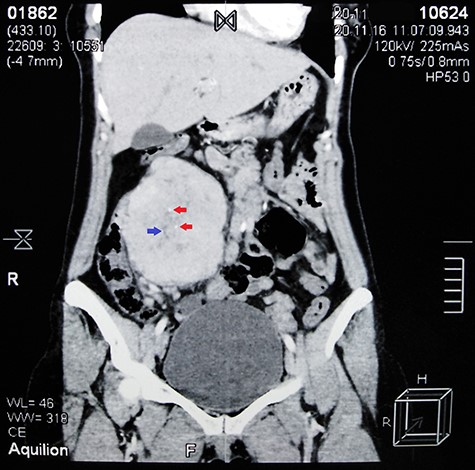

Contrast-enhanced abdominal CT scan shows a large heterogeneous mass adjacent to the inferior margin of the liver measuring (11.5 × 8.5 × 9 cm) and containing calcified areas (red arrows) and necrosis (blue arrow).

Abdominal ultrasound (US) revealed normal findings except for a 9.1 × 7.3 cm heterogeneous mass in the right hypochondrium, and an ~5 cm cystic lesion on the left ovary. Contrast abdominal computed tomography (CT) scan showed a (11.5 × 8.5 × 9 cm) well-defined mass adjacent to the inferior margin of the liver with calcified areas (Fig. 1). Para-aortic lymph nodes were not enlarged.

In UCD, a single, well-defined, enlarged lymph node associated with moderate to intense post-contrast enhancement is often characteristic features of UCD on CT. In addition, calcifications are seen in only 5–10% of CD patients [9].